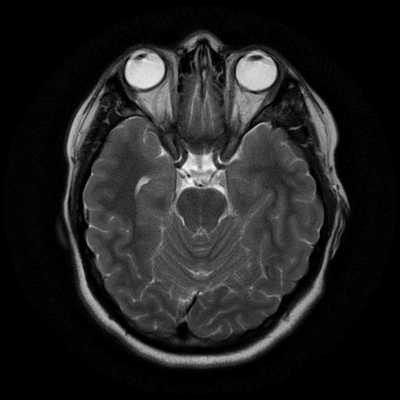

Исследование выполняется в нескольких режимах. Основные из них Т1 и Т2. Изображения, полученные в данных режимах, часто также называют Т1-взвешенными или Т2-взвешенными снимками. Изображения, показанные выше, сделаны в Т1-режиме.

Главное отличие этих режимов - в том, как на снимках отображается жидкость и воздух. В Т1 режиме ткани, содержащие большое количество воды, имеют более темную окраску, в то время как в Т2 режиме они яркие, светлые. Это легко понять, посмотрев на снимки выше - глазные яблоки визуализируются в виде светлых парных округлых образований с одной стороны яркие и светлые, с другой - темные. Следовательно, снимок справа сделан в Т1 режиме, снимок слева - в Т2. Также существует разница в том, как в этих режимах отображается серое вещество головного мозга. В Т2 режиме оно светлее, чем белое вещество.

На самом деле режимов намного больше - FLAIR, DWI, STIR и так далее. Какой-то режим используется для подавления сигнала от богатых жиром тканей, какой-то - для изучения плотности распределения протонов в тканях, третий - для оценки броуновского движения молекул воды. Вот почему полный курс МРТ-диагностики для врачей длится не один месяц.